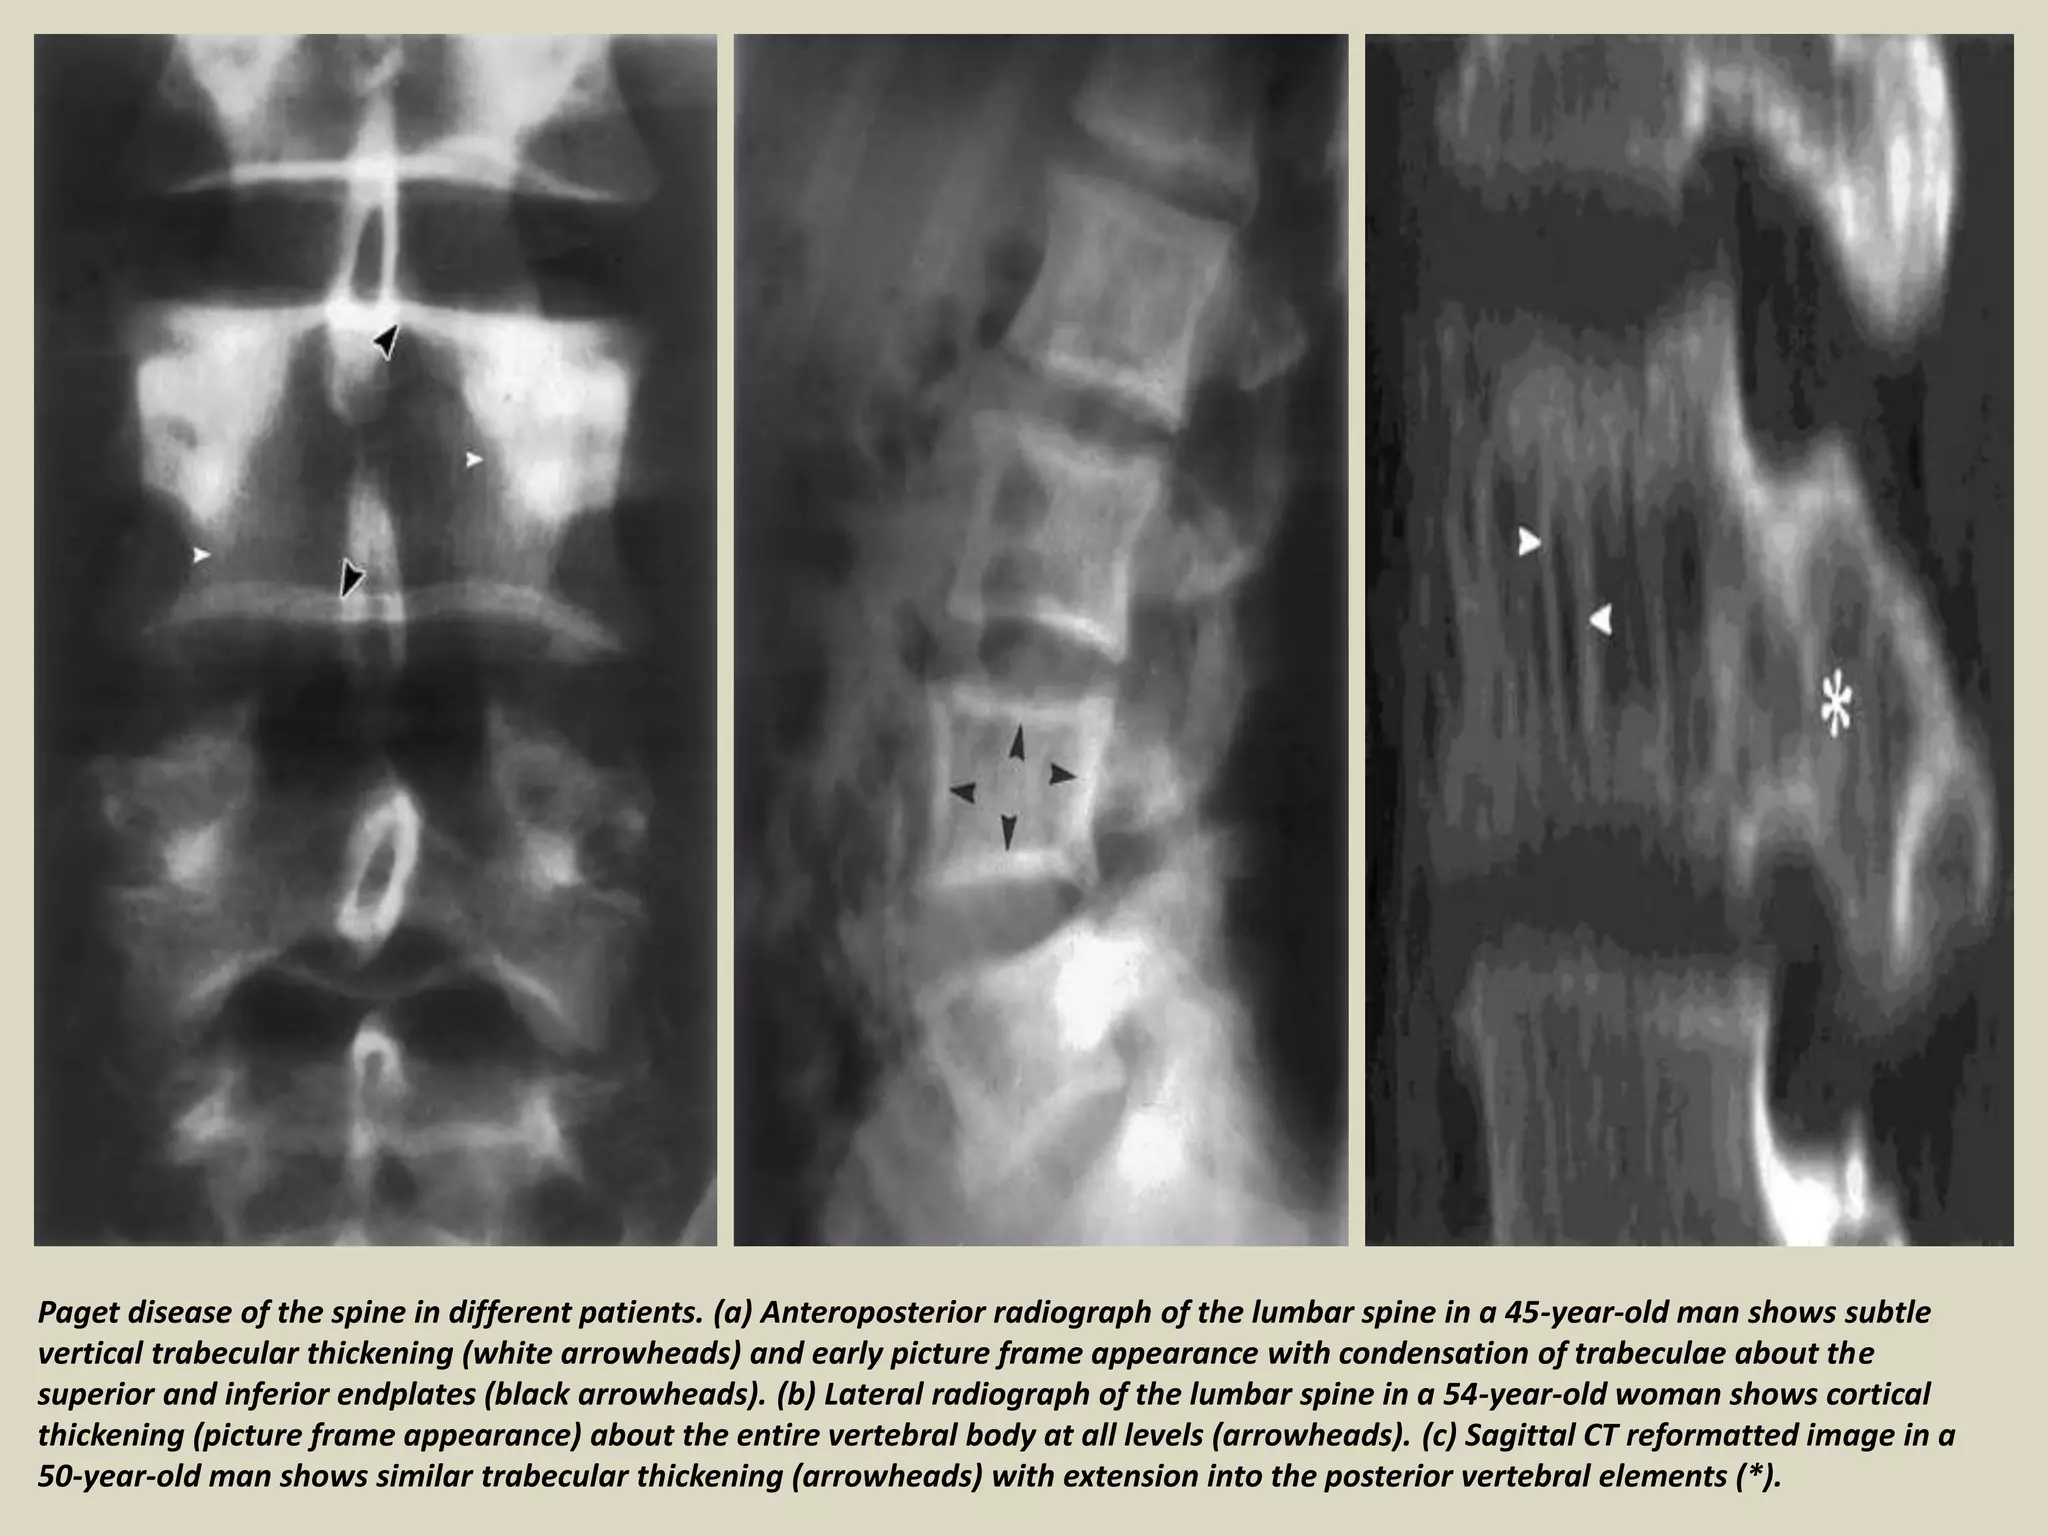

Paget disease of the spine in different patients. (a) Anteroposterior radiograph of the lumbar spine in a 45-year-old man shows subtle

vertical trabecular thickening (white arrowheads) and early picture frame appearance with condensation of trabeculae about the

superior and inferior endplates (black arrowheads). (b) Lateral radiograph of the lumbar spine in a 54-year-old woman shows cortical

thickening (picture frame appearance) about the entire vertebral body at all levels (arrowheads). (c) Sagittal CT reformatted image in a

50-year-old man shows similar trabecular thickening (arrowheads) with extension into the posterior vertebral elements (*).

Paget disease ofthe spine in different patients. (a) Anteroposterior radiograph of the lumbar spine in a 45-year-old man shows subtle vertical trabecular thickening (white arrowheads) and early picture frame appearance with condensation of trabeculae about the superior and inferior endplates (black arrowheads). (b) Lateral radiograph of the lumbar spine in a 54-year-old woman shows cortical thickening (picture frame appearance) about the entire vertebral body at all levels (arrowheads). (c) Sagittal CT reformatted image in a 50-year-old man shows similar trabecular thickening (arrowheads) with extension into the posterior vertebral elements (*).